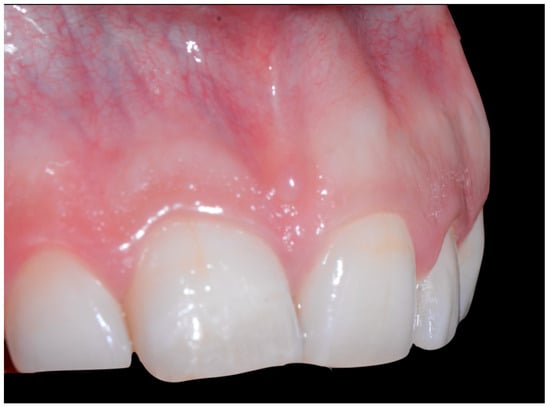

A 40-year-old patient presented with discomfort in tooth 31, citing past orthodontic treatment. As shown in Figure 11, the patient was in Class I and had poor oral hygiene associated with the presence of calculus in the incisivo-canine region. The root of 31, visible to its apex, was out of the bone and associated with severe gingival recession (Cairo RT2). Teeth 41 and 42 also showed gingival recession (Cairo RT2 and RT1).

Figure 11.

Severe wire syndrome. Frontal and lateral views.

Figure 12 and Figure 13 show a difference in the height of the free edges of the mandibular incisors and the extent of root visibility of 31.

Figure 12.

Severe wire syndrome. Frontal view.

Figure 13.

Severe wire syndrome. Lateral views.

No retainer was present in the maxilla, only a residual mandibular retainer, still bonded to 32 and 42, was visible (Figure 14), as well as incisal crowding and a difference in the visibility of the buccal and root surfaces of 41 compared to the contralaterals. In this extreme clinical situation, a severe and terminal wire syndrome on tooth 41, the “X-effect” type, was observed.

Figure 14.

Severe wire syndrome. Occlusal view.

In the present case of severe WS, generalized moderate periodontitis was diagnosed, except on the mandibular incisors, which showed a more severe attachment loss. This can be explained by the presence of the WS, which aggravates the pathological process. The presence of bacterial and calculus deposits on the incisors was certainly important, but it alone cannot explain the severity of tissue destruction, particularly on 31. This case highlights the problem of the multi-factorial etiology of WS.